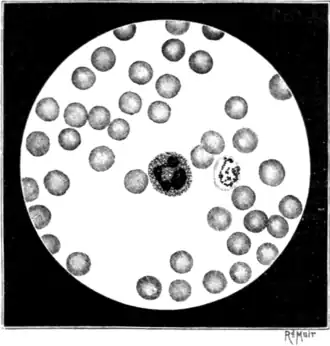

For a thorough appreciation of the principles on which blood examinations for the demonstration and study of the malaria parasite should be conducted, it must be borne in mind that the parasite is intracorpuscular. To see it, therefore, it is necessary, particularly for the beginner, so to dispose the corpuscles in the preparations that a proportion of them shall lie flat on the slide, in a single layer, and presenting their surfaces, and not their edges, to the observer (Fig. 16). It is mainly from ignoring this fundamental principle that so many fail to find the parasite.

On examining successful preparations with the microscope it will be found that the central zone or area contains few or no blood-corpuscles. This zone may be designated the "empty zone." Proceeding outwards from this we come on an area occupied by scattered, isolated, compressed, and much-expanded corpuscles—the "zone of scattered corpuscles." Farther out the corpuscles become more numerous and less expressed (Fig. 16). Gradually, as we trace the film still farther outwards, the corpuscles are found approximated to each other, until, finally, the peripheries of the corpuscles are mostly in touch—the "single-layer zone." Farther out the corpuscles, though still lying flat, are found to overlap each other or are piled one on the top of the other—the "zone of heaped-up corpuscles." Beyond this zone the corpuscles are arranged in rouleaux the "zone of rouleaux." At the extreme margin of the preparation the corpuscles tend to break up and run together so as to form a narrow border of free hæmoglobin, the individual corpuscles perhaps being indistinguishable the "zone of free hæmoglobin." Each of these zones should be studied, for each may afford special information about the malaria parasite.

cent.) and prolonged staining. The stain is dropped on the slip and covered with a watch-glass; after six to eight hours it is washed off with water, the slide dried, and a cover-glass applied with xylol balsam.On examining with a one-twelfth immersion lens slides prepared with methylene blue,[2] the nuclei of the white corpuscles are seen to be very deeply stained, the protoplasm of the white corpuscles is very lightly stained, whilst the parasites are stained an intermediate tint, and show up sharply enough in the faintly tinted red blood-corpuscles (Figs. 2, 16, 20). Contrast staining with eosin is uncertain in its results in methylene-blue preparations; even in practised hands good preparations are the exception. For ordinary purposes I do not recommend it; it is superfluous, troublesome, and unreliable.